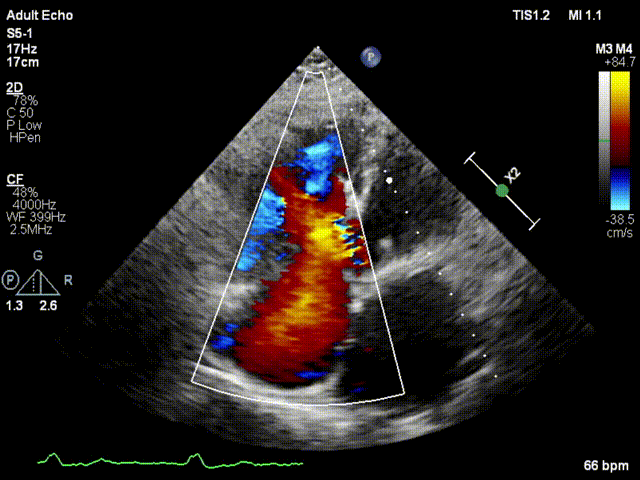

本次接受治療的患者是一名74歲的女性,14年前因風濕性心臟病行二尖瓣生物瓣植入術,合并房顫。近3年來反復因腹脹、納差、下肢水腫入院,藥物治療欠佳。心臟超聲顯示三尖瓣極重度反流(有效反流口面積:0.76cm²,反流容積:79ml),繼發(fā)性右房室增大及上、下腔靜脈增寬(右房上下徑*左右徑:52*41mm,右室左右徑:46mm,下腔靜脈:29mm),右室收縮功能正常,肺動脈收縮壓 43mmHg,左心室射血分數(shù)73% ?;颊呒韧_胸手術史,術前評估STS 評分為7.02分,CRS 9分,無法接受體外循環(huán)下三尖瓣外科手術。面對這一傳統(tǒng)治療無法解決的困境,葛均波院士及其團隊周達新教授、潘文志教授、張源博士、陳莎莎博士及心超室的潘翠珍教授、李偉教授經過討論決定,采用創(chuàng)新的Lux-Valve Plus系統(tǒng)為患者進行經血管三尖瓣置換。

手術在患者全麻狀態(tài)下進行,采用經右側頸靜脈作為入路,將裝載有人工瓣膜的輸送器緩慢推送至右心房;并在經食道超聲和DSA的引導下小心調整輸送器角度,將輸送器送入右心室;逐步釋放瓣膜錨定裝置和盤片,調整瓣膜位置后,錨定瓣膜完成植入。術后右房壓明顯下降,從術前的25/10(16) mmHg降至術后即刻的12/7(10) mmHg,術后超聲提示人工三尖瓣同軸性良好,固定牢固,無反流及瓣周漏,手術室即刻拔除氣管插管。